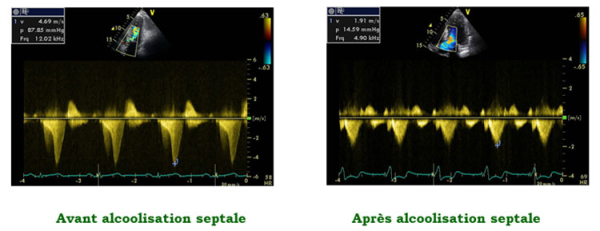

La présence d’une obstruction intra-ventriculaire gauche est inconstante dans les CMH et permet d’opposer les formes obstructives (CMHO) et non obstructives. L’obstruction peut être présente à l’état basal, ou n’apparaître que lors de la manœuvre de Valsalva, ou pendant ou après l’effort. Une obstruction est définie comme un gradient maximal instantané sous-aortique > 30 mmHg au repos, ou après manoeuvre provocatrice, et hémodynamiquement significative au-delà de 50 mmHg. Cette obstruction sous-aortique est fortement corrélée aux symptômes et doit être recherchée de façon rigoureuse, car elle est la cible des principales thérapeutiques de la CMHO (bétabloquants, alcoolisation septale, chirurgie de réduction septale, et bientôt de nouvelles molécules comme les inhibiteurs sélectifs de la myosine (Figure 2).

Figure 2 : régression de l’obstruction intra-ventriculaire gauche mesurée au doppler continu après alcoolisation septale